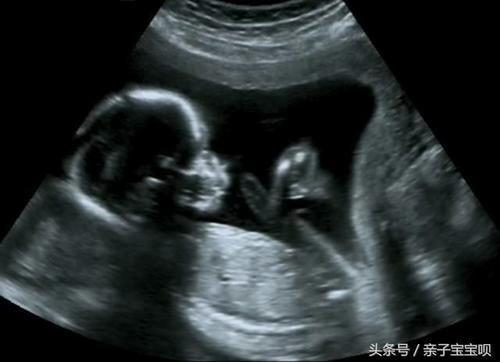

陆思诚把己经怀孕六个月的白韵兮带到医院

彩超室

陆思诚看着那个B超的小人儿笑了笑

医生说宝宝很健康没什么问题,夫妻俩回基地时遇到了明神